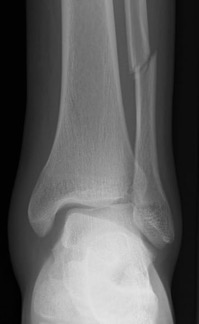

# cheville: score de Weber

Fracture de type Weber A : fracture en-dessous de la syndesmose ; l`articulation est encore mobile.

Fracture de type Weber B : fracture à hauteur de la syndesmose ; souvent le ligament est touché à cause d'un mouvement de rotation mais l`articulation peut encore être mobile.

Fracture de type Weber C : fracture au-dessus de la syndesmose ; le ligament est déchiré à cause d'un mouvement de translation latérale.